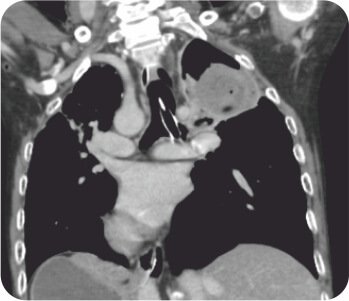

থোরাসিক এনজিওগ্রাম সহ CT বুকে হাইপারট্রফিড কোলাটারাল ধমনী সহ দ্বিপাক্ষিক গহ্বরের ক্ষত প্রকাশ করে যা প্রধানত ডান উপরের লোব গহ্বর সরবরাহ করে। FOB করা হয়েছে ডান উপরের লোব ব্রঙ্কাস থেকে সক্রিয় রক্তপাত দেখায়।

সিটি থোরাসিক এনজিওগ্রাফ